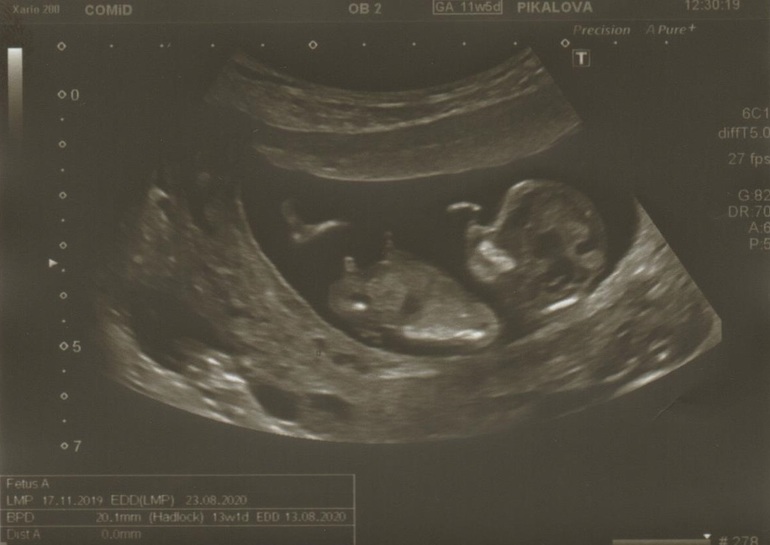

Мальчик?

Срок 13,3. Была сегодня на скрининге, почти не переросли его)) по узи все хорошо, а кровь будет завтра.

Девочки, врач так уверенно сказала «предполагаю мальчика!». Я очень удивилась))) скажите, а вы кого предполагаете по фото?)?